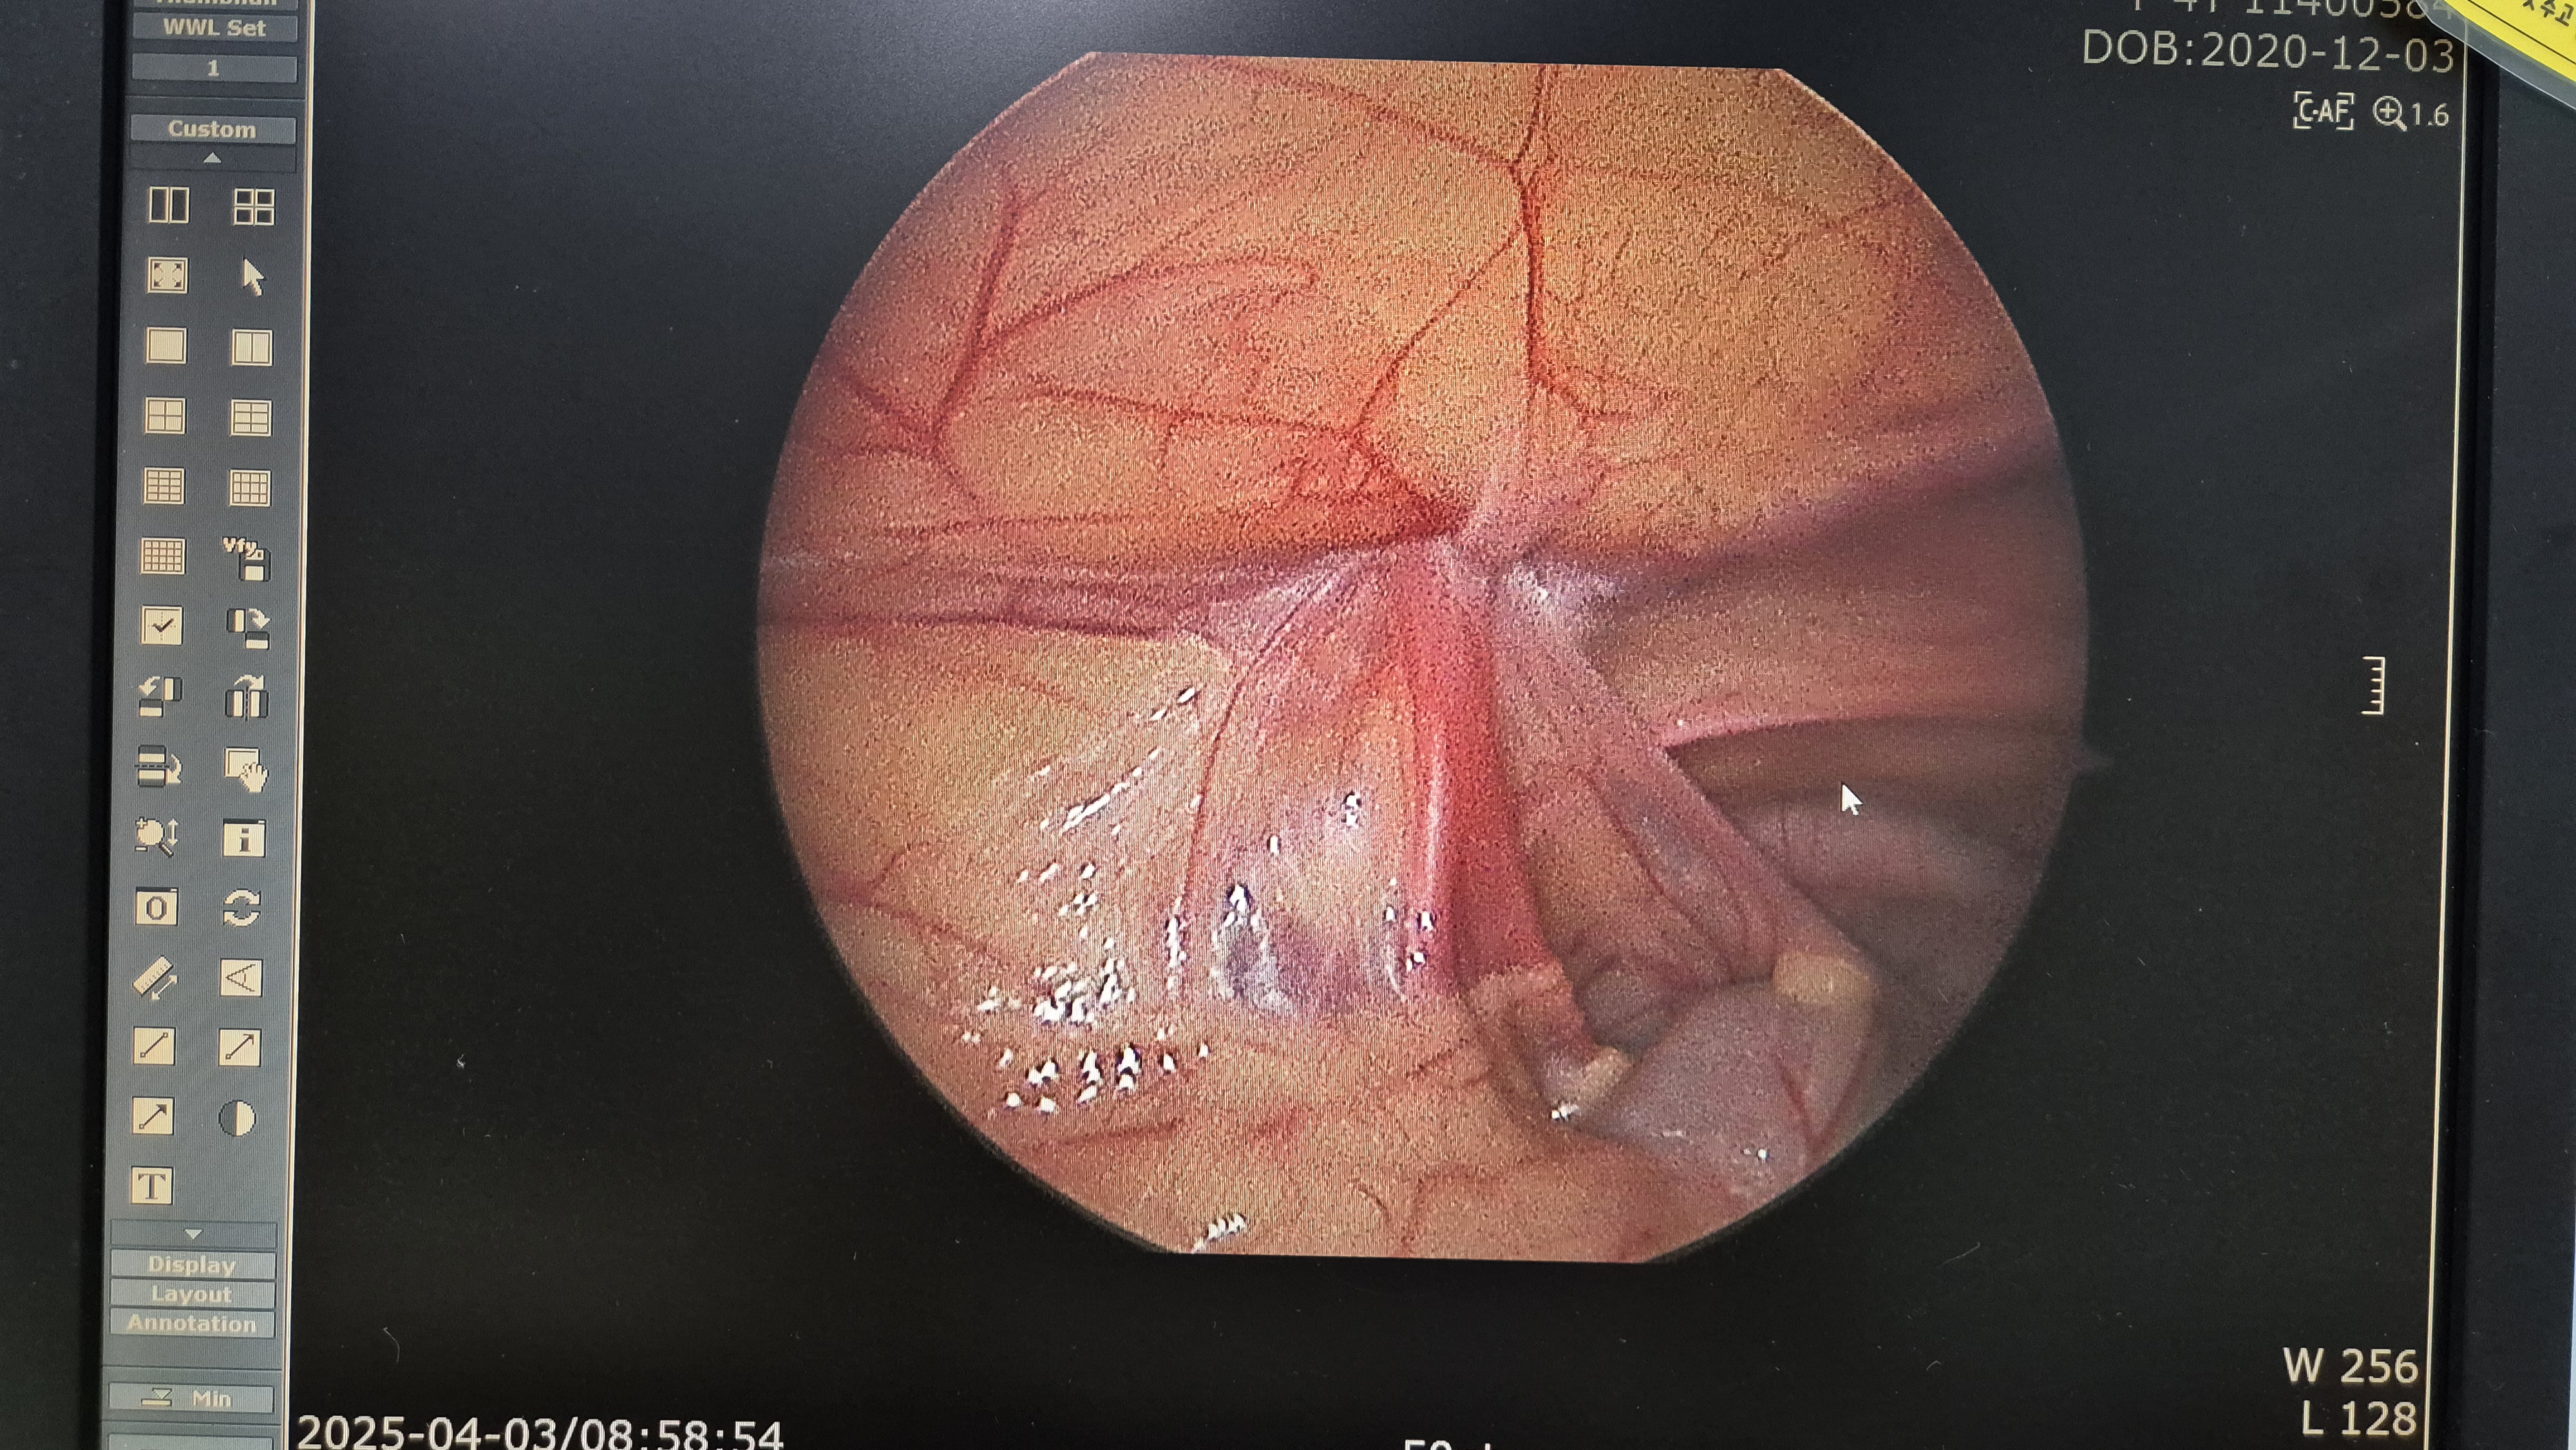

교정후.

교정후.